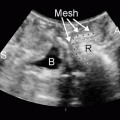

Dynamic graciloplasty (covered in Chap. 30) is a complex procedure requiring specific expertise, which is expensive and often associated with considerable morbidity and a moderate operative revision rate [40–46]. The stimulator required to change the muscle fibers to a slow-twitch muscle is currently unavailable for clinical use in the US. Injectable bulking agents using a range of bioaugmentable agents designed to supplement the disrupted internal anal sphincter have been shown to be effective in some studies but are not presently approved in the US for the specific treatment of fecal incontinence [47–50]. This topic also is covered in Chap. 33. Other potential alternatives being investigated for this cohort of recurrent patients include the use of a transobturator rectal sling (which is undergoing trials in the US) [51] and some novel animal work using muscle progenitor cell autograft transplantation, which has shown accelerated myofiber repair in the damaged sphincters of rabbits along with enhanced sphincteric electromyographic activity [52].